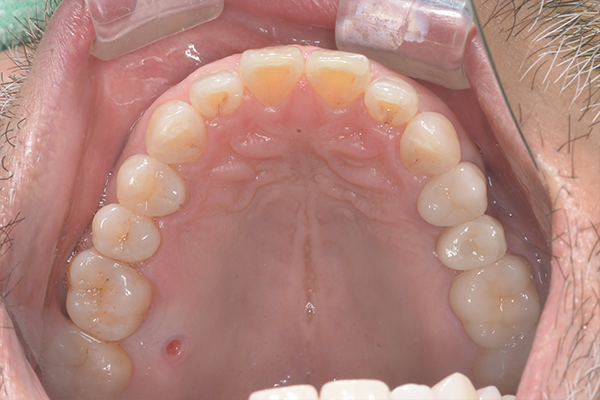

治療前〜治療後のレントゲン写真

患者様の要望過去に治療したブリッジを外し咬み合わせの平面を整えて、被せ物や詰め物を綺麗にしたい。

治療期間10ヶ月

治療費用1,600,000円

治療内容インプラント2本、アンカースクリューを用いた部分矯正、

セラミックによる補綴治療

治療のリスクセラミックの破折の可能性